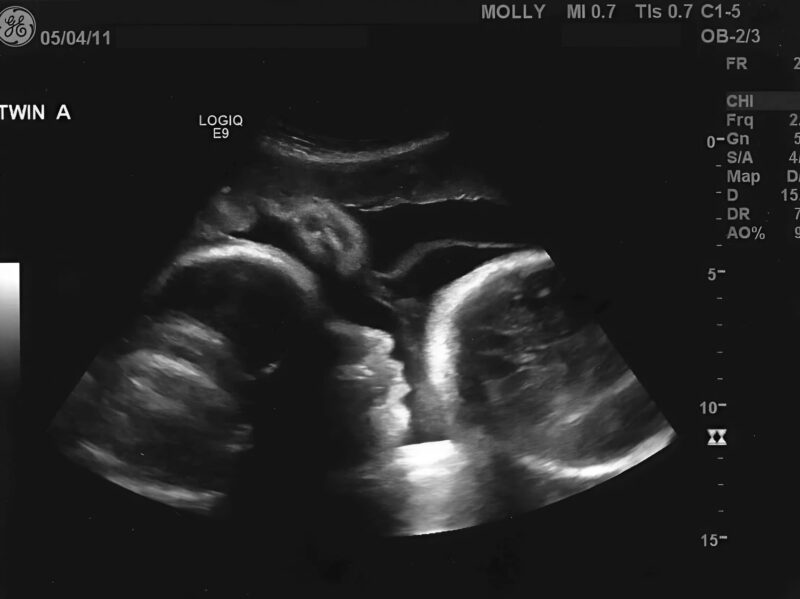

Further testing confirmed that the abdominal swelling was caused by a serious medical condition requiring prompt attention. The earlier assumptions did not align with the actual diagnosis.

This explanation provided clarity regarding the physical changes she had experienced, as well as the discomfort that had developed over time.